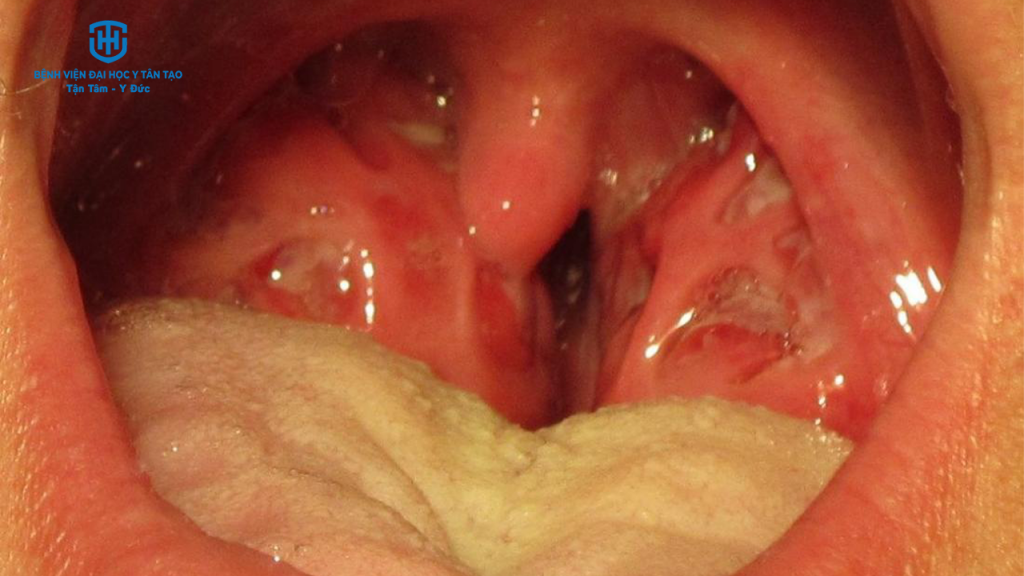

Viêm họng do liên cầu khuẩn là một bệnh nhiễm trùng cấp tính ở miệng họng và amidan. Đây là một bệnh nhiễm trùng rất dễ lây lan do một loại vi khuẩn gọi là Streptococcus nhóm A (strep nhóm A). Khi điều trị thường cần đến thuốc kháng sinh. Những người bị viêm họng do liên cầu khuẩn có khả năng truyền bệnh cho người khác. Trong vài trường hợp, người sau khi bị nhiễm bệnh nhưng không có triệu chứng vẫn có thể lây nhiễm sang người khác.

TRIỆU CHỨNG CỦA VIÊM HỌNG DO LIÊN CẦU KHUẨN

Các triệu chứng phổ biến của viêm họng liên cầu khuẩn bao gồm:

- Sốt, đau đầu.

- Đau họng, đau nhiều khi nuốt.

- Ho.

- Chán ăn, ăn không ngon.

- Mệt mỏi.

- Có thể kèm đau bụng, buồn nôn hoặc nôn.